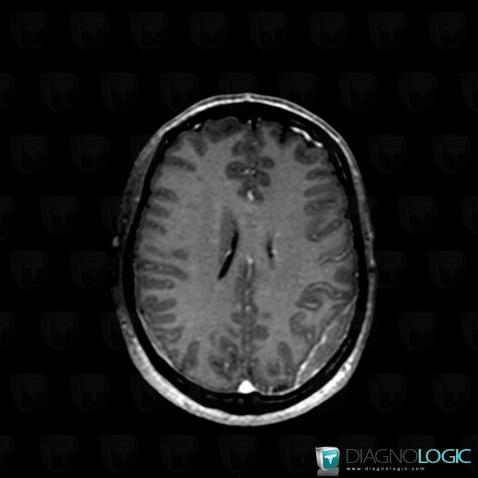

Voici les informations spécifiques à l'image clé ci dessus:

- Diagnostic Lymphome , Localisation(s) Espaces peri cérébraux supratentoriels, comportant les gammes Réhaussement méningé focal, Lésion extra axiale supra tentorielle